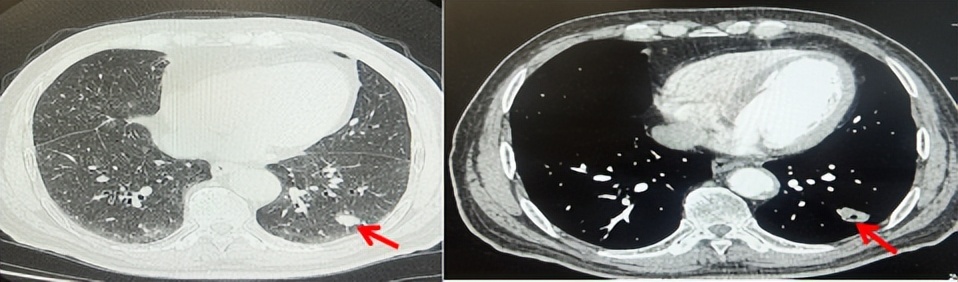

69岁男性,无糖尿病、高血压、心脏病等基础疾病,无吸烟、饮酒史,无肿瘤家族史。2023.06.07行胸部CT检查:右肺上叶胸膜下见肿物影,大小约33mm×22mm,边缘可见分叶,考虑恶性病变可能性大,双肺间质改变(如图1)。2023.06.14行“单孔胸腔镜下右肺上叶切除、肺门及纵隔淋巴结清扫、胸膜粘连松解术”;术后病理:(右肺上叶)腺癌(低分化,实体型占60%,不良腺体占40%),局灶伴神经内分泌标记表达(CD56、Syn),可见STAS及胸膜侵犯,未见确切神经侵犯及脉管内癌栓;(气管切缘)净;(淋巴结)未见转移癌0/26(2组0/2;4组0/6;7组0/2;对侧7组0/8;10组0/2;11组0/3;12组0/2;13组0/1)。术后分期pT2aN0M0 IB期,术后NGS基因检测:无驱动基因突变,PD-L1(22C3)TPS<1%。术后定期复查。

图1:患者手术前(2023.06)胸部CT肺窗及纵隔窗